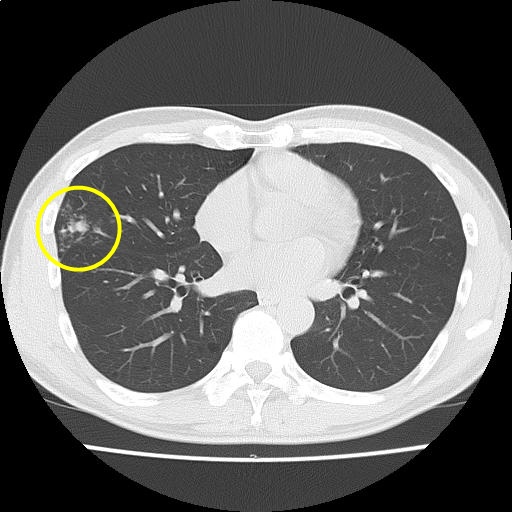

CT画像46

(44/225)